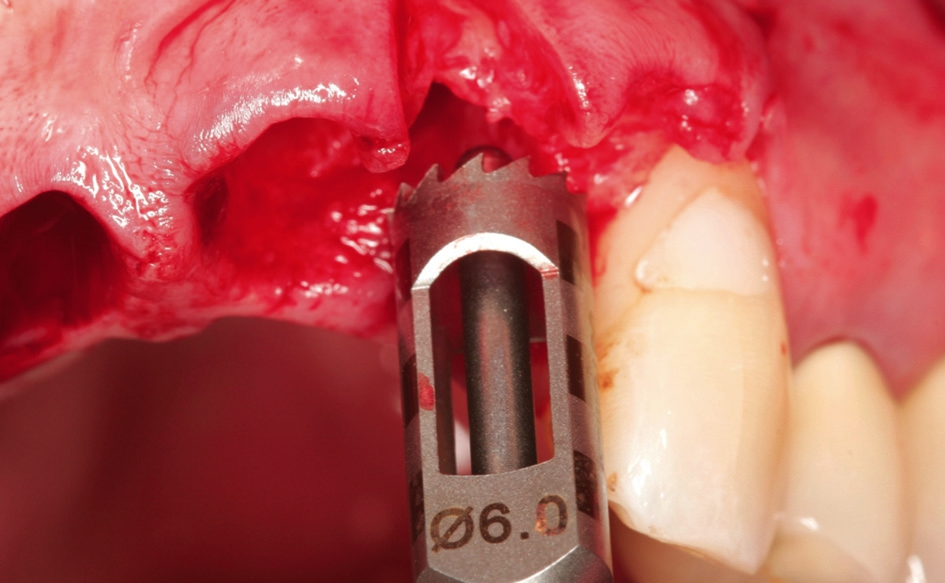

Nach Extraktion der Zähne 12, 22, 11, 21 wurde mit dem Behandlungsprotokoll für maxgraft® bonering begonnen. Nach Pilotbohrung zur Festlegung der Implantatposition wurde mit einem 6 mm Trepan die Augmentationsstelle des maxgraft® bonerings vorbereitet (Abb. 5). Danach folgte das Planieren des Ringbettes mit einem 6 mm Planator, um ein flaches Ringbett zu generieren (Abb. 6).